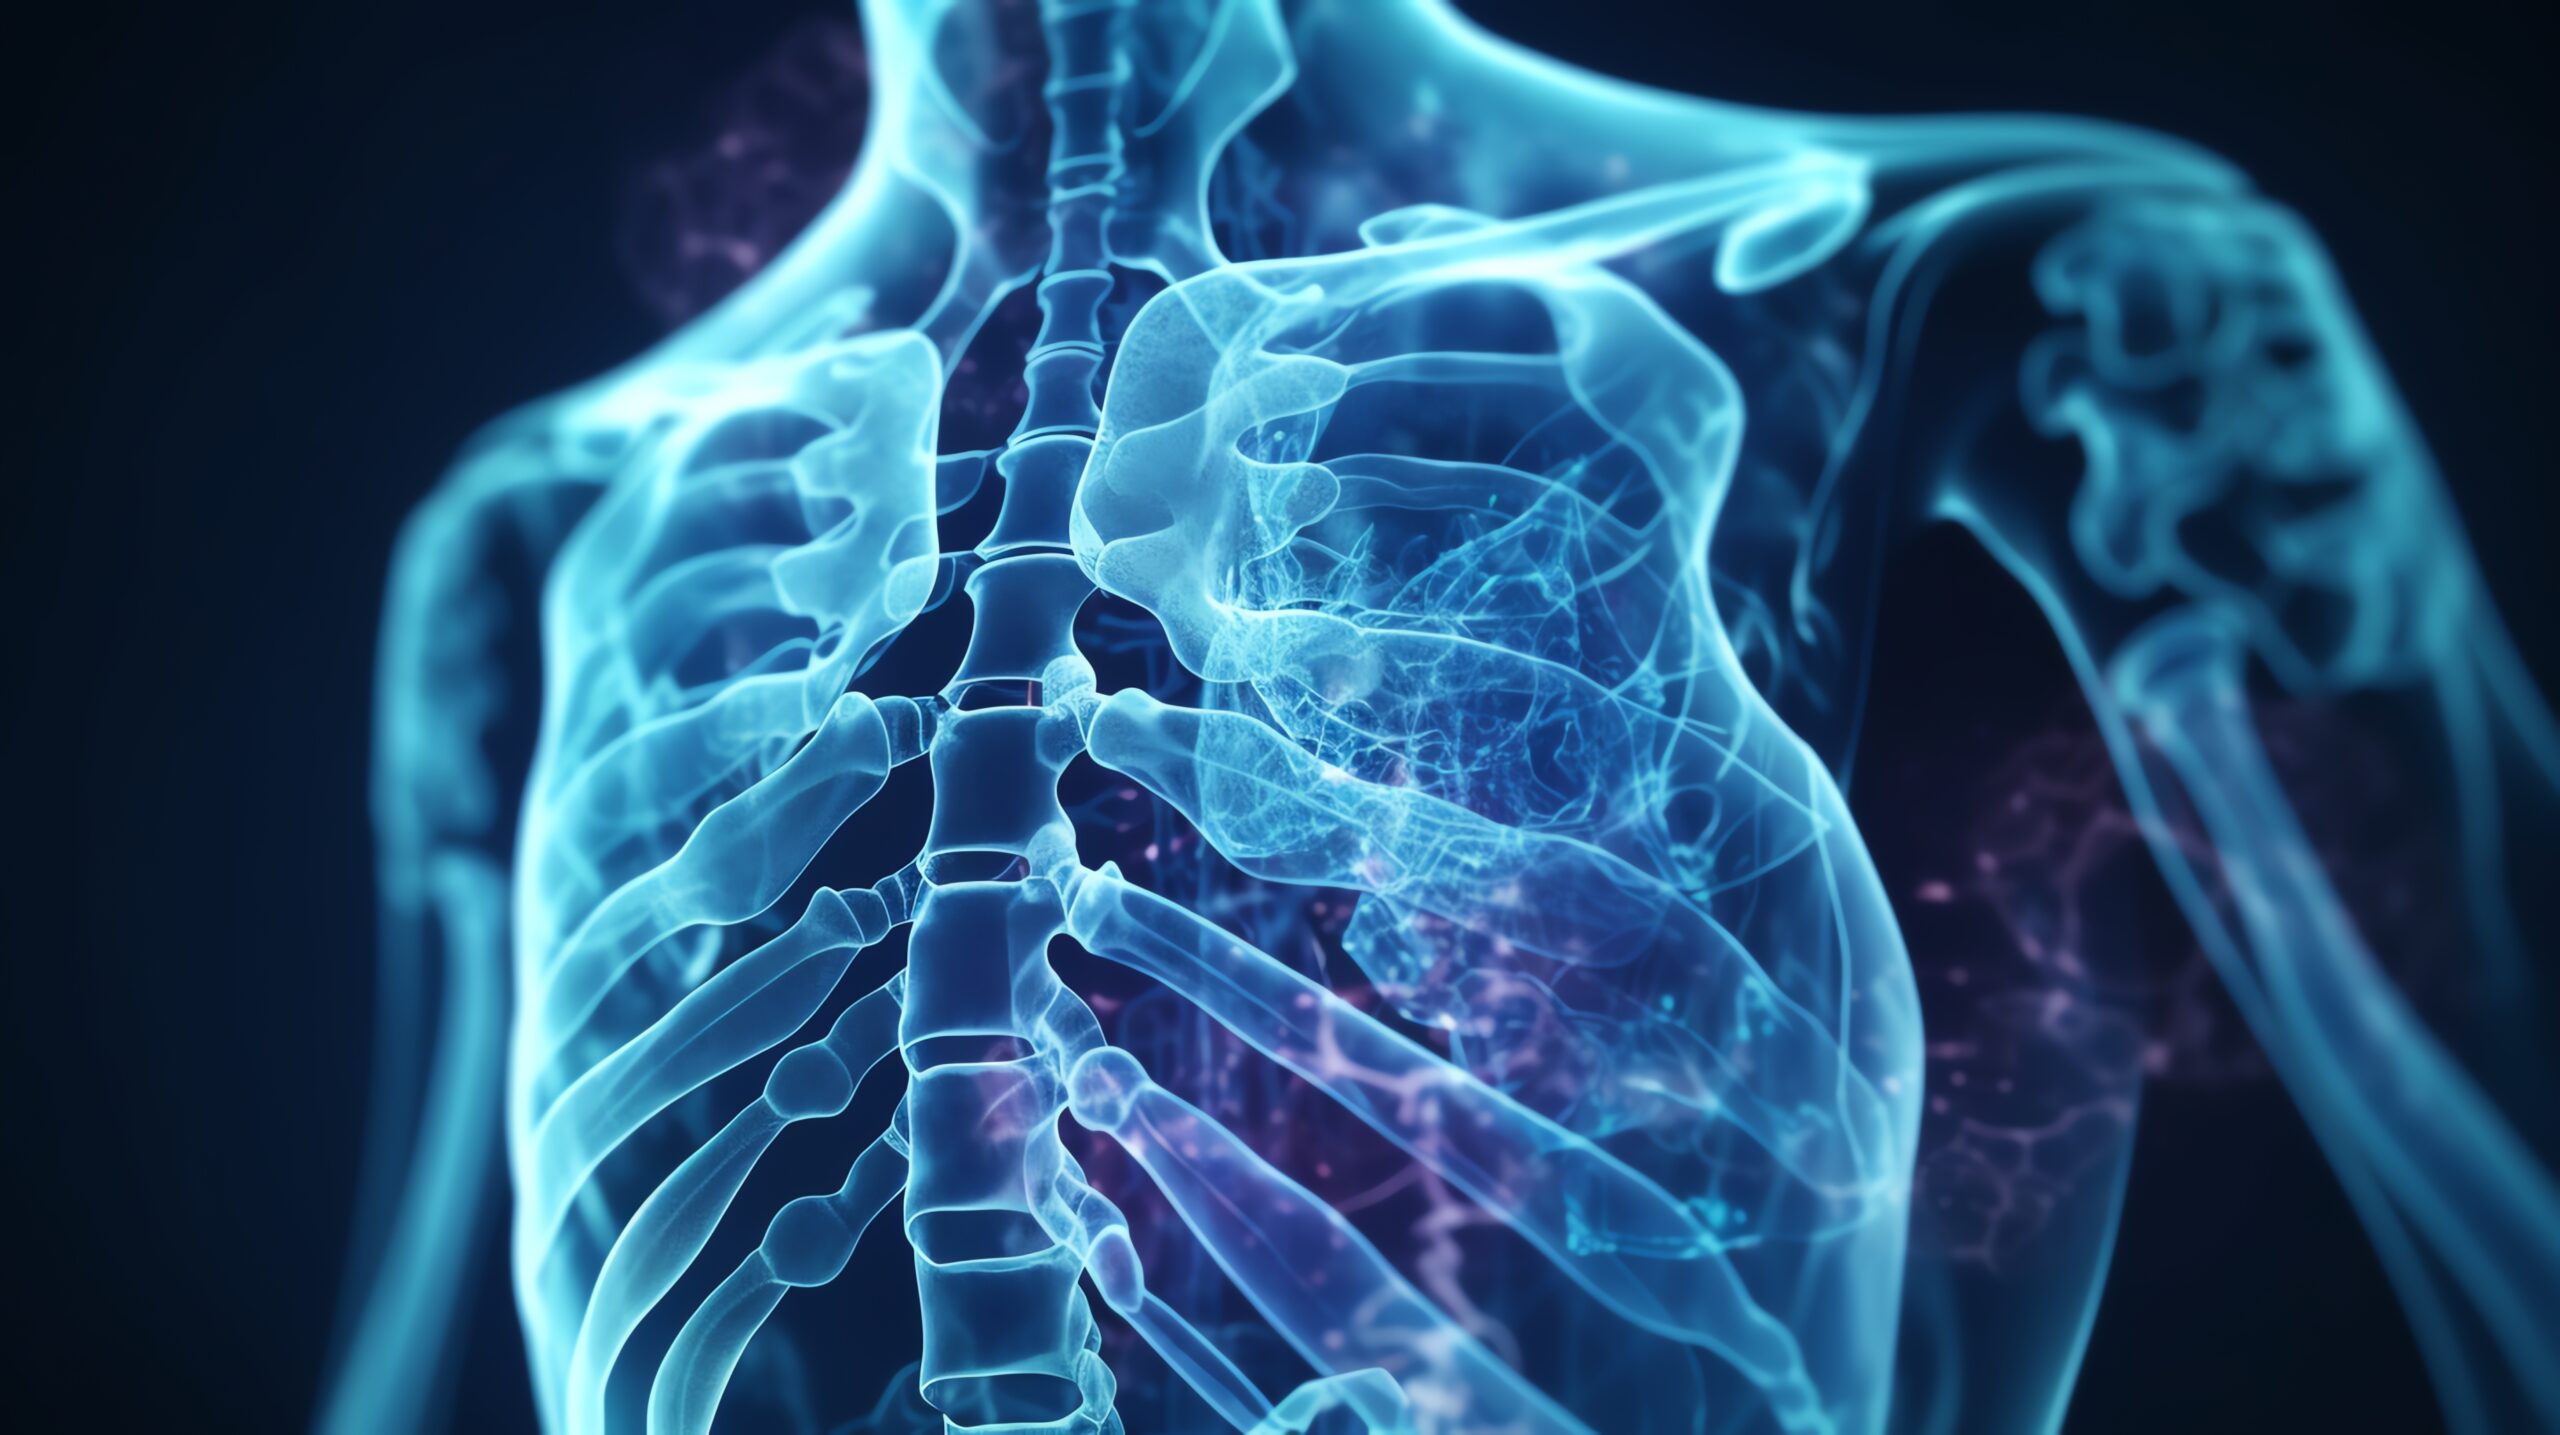

Digital Radiography (DR)

Advanced Digital Radiography (DR) at Himalayan Diagnostics provides fast, safe, and high-quality X-ray imaging for accurate diagnosis with minimal radiation exposure.

Advanced Digital Radiography (DR) at Himalayan Diagnostics provides fast, safe, and high-quality X-ray imaging for accurate diagnosis with minimal radiation exposure.